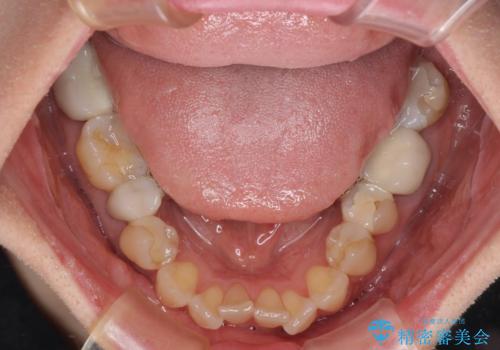

- 矯正装置

- 審美装置

- 治療期間

- 1年10ヶ月

舌突出癖により、上下前歯がなかなか接触せずに治療期間を要しましたが、舌のトレーニングにより無事に治療を終えることができました。